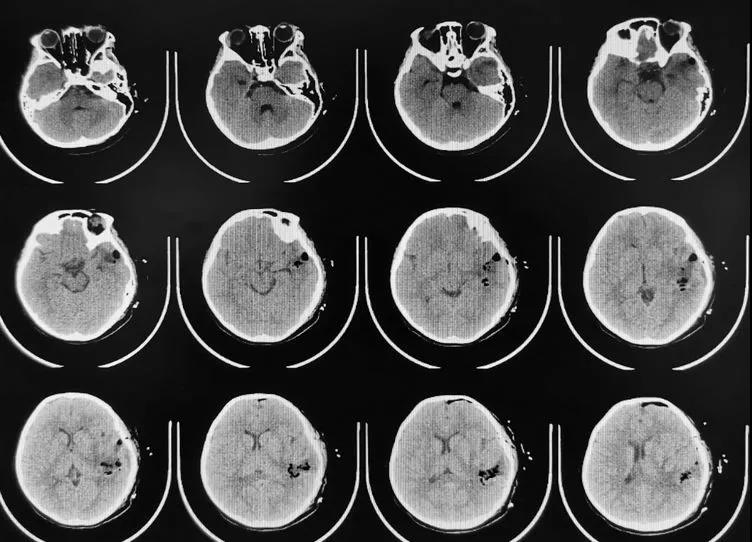

9月7日,外院急诊送来了一名脑出血的女童,年仅9岁,患儿6个小时前无诱因突发“意识障碍伴四肢无力、胡言乱语”,家长急送当地医院进行头颅CT检查,提示“左颞叶脑出血”。

为进一步治疗急转来锡林郭勒盟医院,入院时患儿意识模糊、双侧肢体肌力减弱以右侧明显,复查头颅CT后“左颞叶脑出血,量较前对比无增加”,脑科中心脑血管病团队在高天主任组织下进行了病情讨论:儿童发生急性脑出血有很大比例是血管畸形、烟雾病及少见的肿瘤脑卒中,如果没有术前充分的影像检查而去贸然做手术,很可能就是畸形无法处理还要二次手术或术中出血不可控危及生命;初步诊断:左颞叶脑出血、动静脉血管畸形破裂?医嘱给与脱水降颅压、止血等对症处理,完善脑血管造影(DSA)检查明确病因诊断后,再进行下一步的治疗措施。

↑入院CT检查